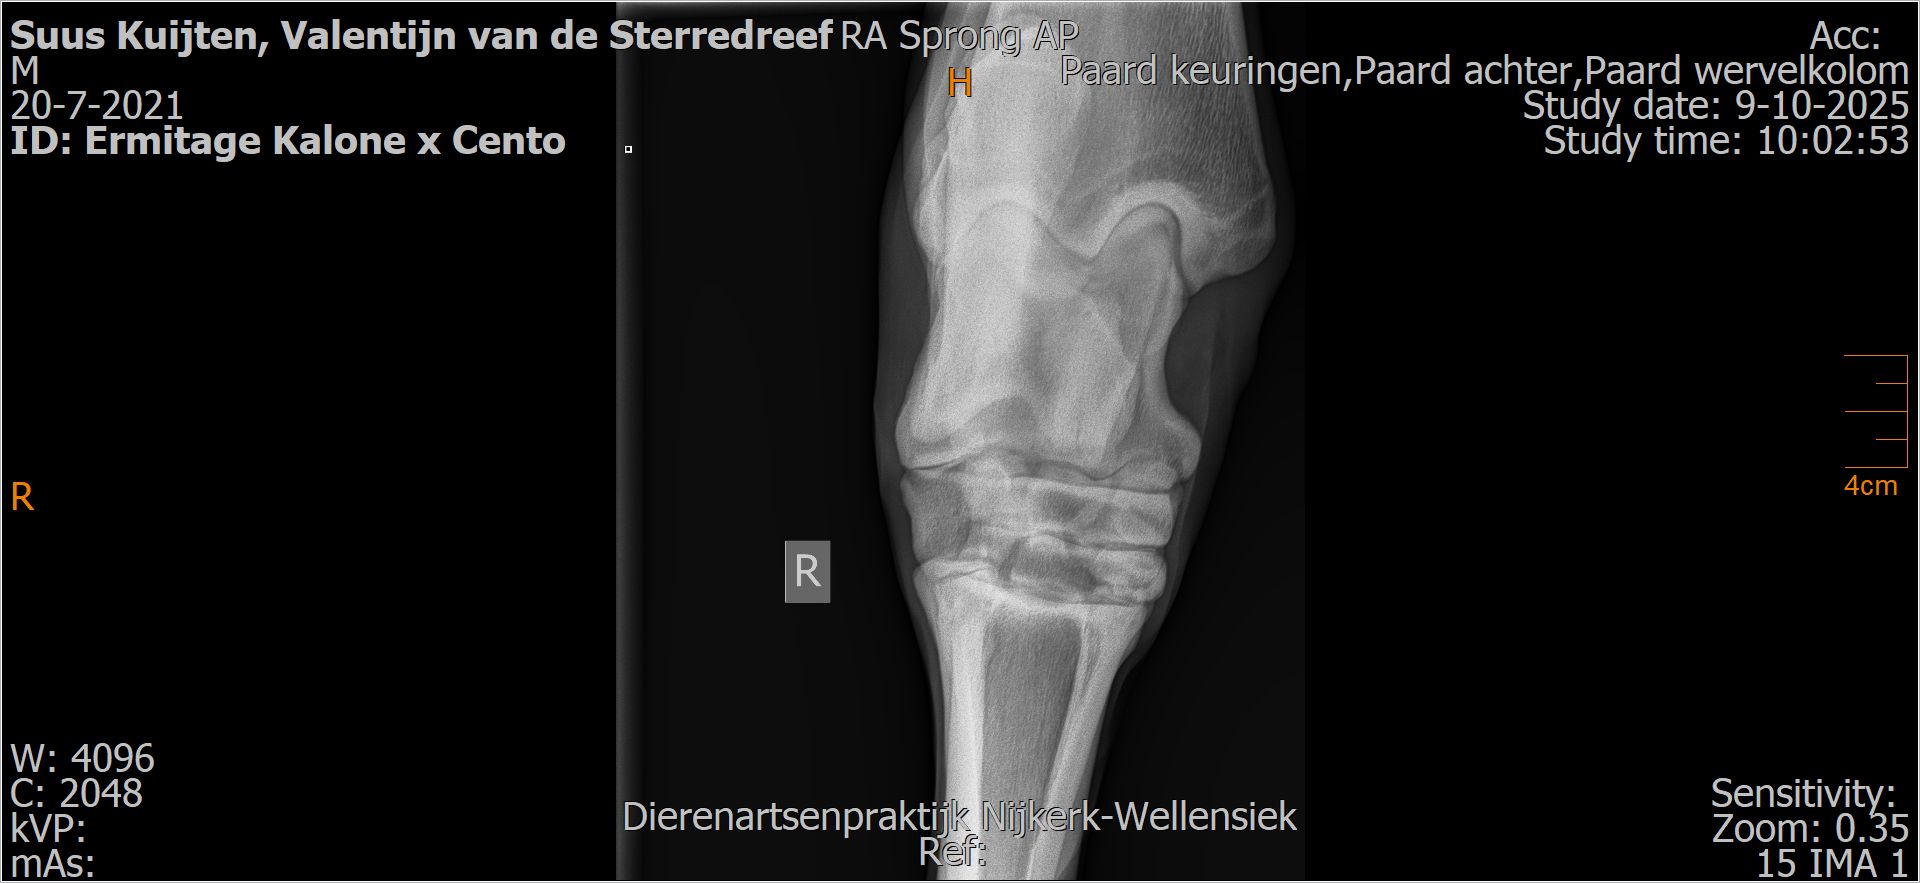

Valentijn van de Sterredreef

Leeftijd:

4

Röntgenfoto’s